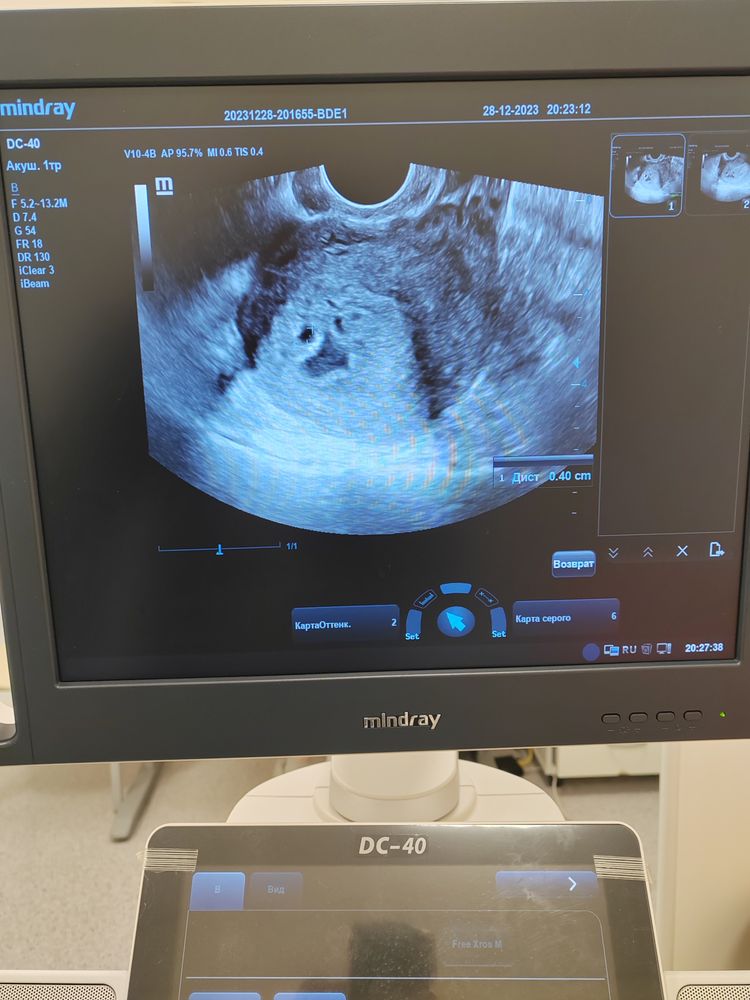

Маточная или внематочная беременность?

Была сегодня на УЗИ. По месячные срок 5 недель и 4 дня. Врач долго крутила-вертела датчиком, сказала, что непонятно, маточная или внематочная беременность... Врач ещё говорила, что в матке что-то расширено, но бывают случаи, когда через неделю приходят пациентки, а там все сомкнулось и уже развивается плод... Эндометриоз и матка загнута кзади... На всякий случай прописала Утрожестан. ХГЧ завтра я сдать не смогу, а там уже праздничные дни... В субботу записана к врачу. Теперь переживаю, что у меня что-то расширено и ничего не разглядели...

По тому что есть, а это эндометрий и образование в матке, то беременность маточная, просто очень раннего срока.

Может просто срок по М и реальный не совпадают? Потому что таком сроке уже пя должно быть видно. Сегодня была на узи 5+2 плодное яйцо уже хорошо видно, эмбрион только не разглядеть.

Маточную и внематочную беременность узистка конечно должна была быть разглядеть. У меня на сроке 4 недели увидела, что б маточная, а вот эмбрион не визуализировался т.к срок слишком мал. Если есть возможность сходит платно на узи.